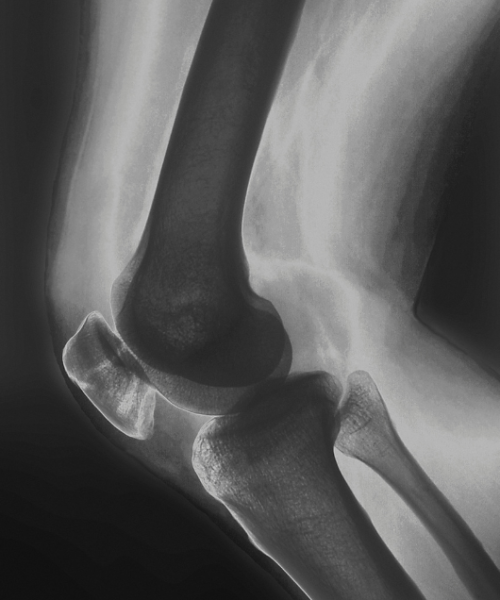

Artroza kolena

Artroza je zdravstveno stanje pri katerem se obrabi naravno oblazinjenje med sklepi, torej hrustanec. Ko pride do tega stanja se zgodi, da kosti sklepov drgnejo ena ob drugo z manj absorpcijskimi učinki hrustanca.

Artrozo kolena povzročajo starost, prekomerna telesna teža, spol (ženske starejše od 55 let), ponavljajoče poškodbe, šport in ostale bolezni (artritis, motnje metabolizma, presežek rastnega hormona).

Ljudje pri tem stanju zaznavajo bolečino ob aktivnostih, otekline, občutek toplote v sklepu, togost kolena in zmanjšano mobilnost, torej težje vstajanje iz stola, avta, uporabo stopnic.

Diagnostika artroze kolenskega sklepa običajno obsega anamnezo, fizični pregled, rentgenski posnetek, MRI, ultrazvok in funkcionalne teste, najbolj informativni pa je običajno MRI, ki zdravniku pomaga ugotoviti vzrok artroze.

Za lajšanje znakov artroze lahko ljudje veliko naredijo sami. Veliko podporo pa nudi tudi fizioterapija, kjer fizioterapevti naučijo pravilno krepitev določenih mišic in povečanje fleksibilnosti kolenskega sklepa.

Artroza je zdravstveno stanje pri katerem se obrabi naravno oblazinjenje med sklepi, torej hrustanec. Ko pride do tega stanja se zgodi, da kosti sklepov drgnejo ena ob drugo z manj absorpcijskimi učinki hrustanca.  Artrozo kolena povzročajo starost, prekomerna telesna teža, spol (ženske starejše od 55 let), ponavljajoče poškodbe, šport in ostale bolezni (artritis, motnje metabolizma, presežek rastnega hormona).